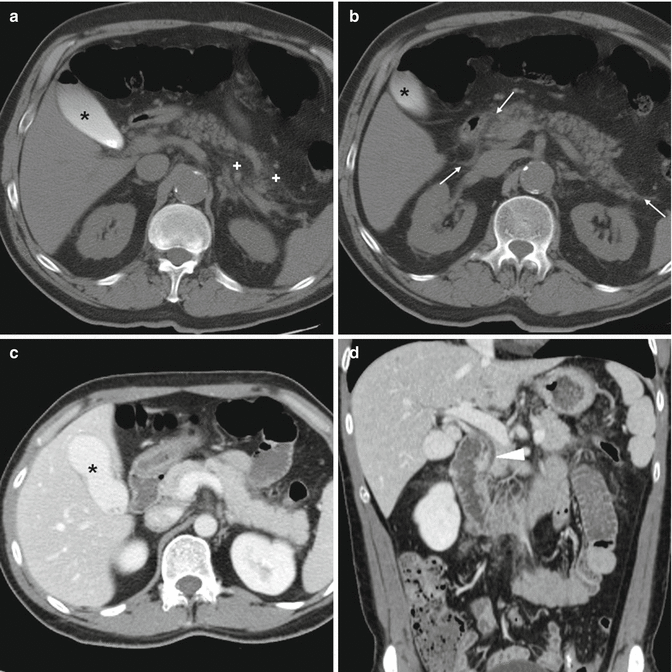

Photo Credit by: bing.com / after ercp stool findings endoscopic complications imaging retrograde

Photo Credit by: bing.com / ercp after stool findings imaging retrograde endoscopic complications

Photo Credit by: bing.com / after ercp stool complications imaging endoscopic findings retrograde